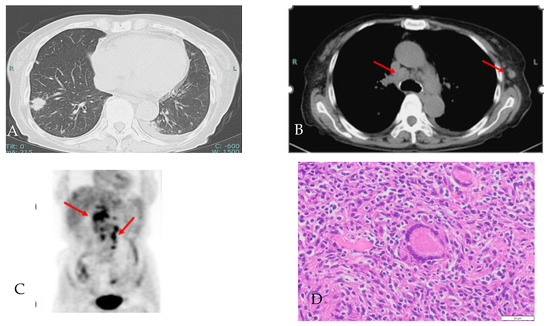

2. Case Presentation Section